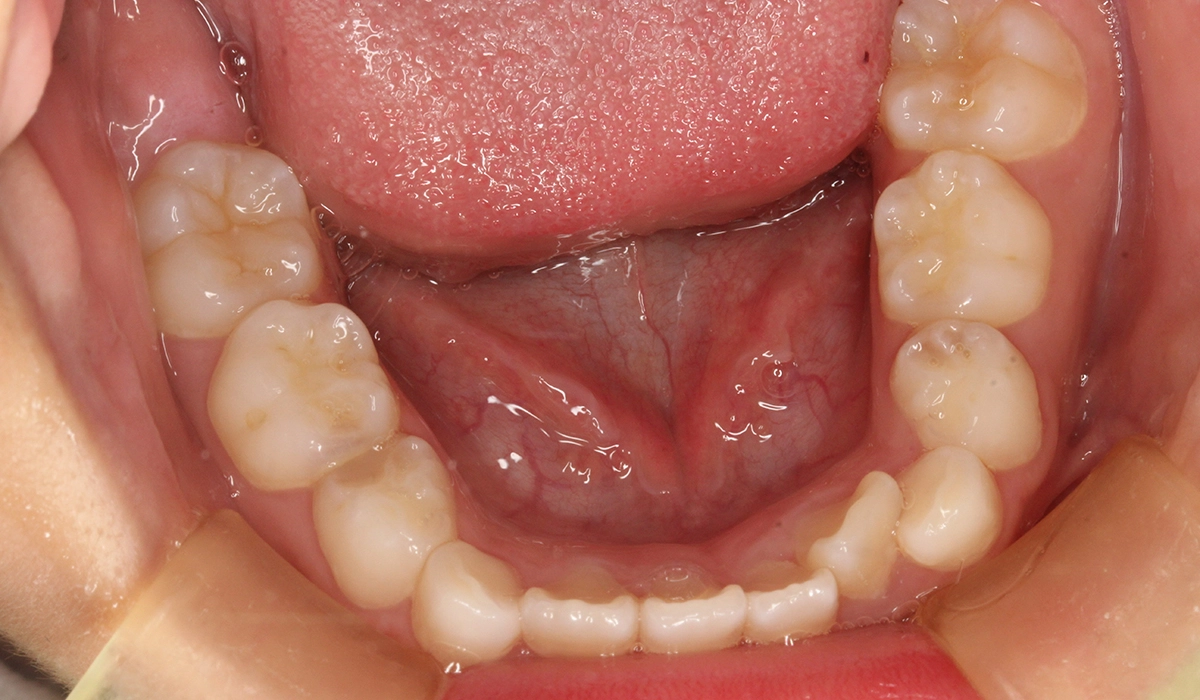

術前:下顎